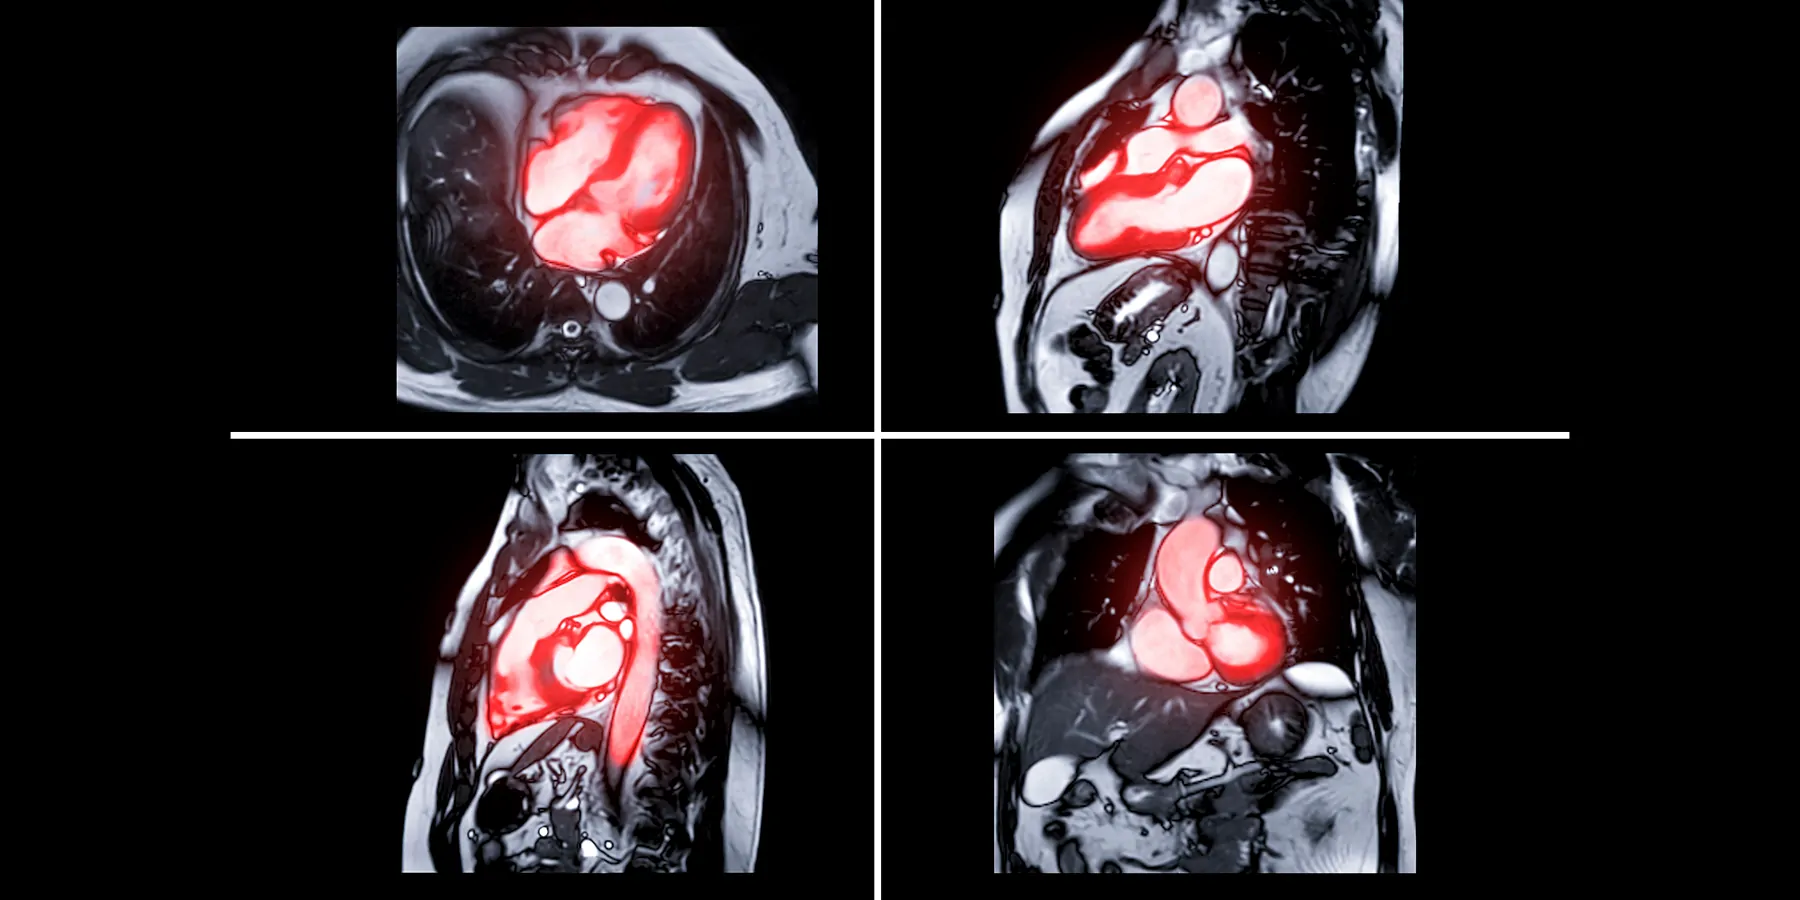

A new form of magnetic resonance imaging (MRI) that makes cancerous tissue glow in medical images could help doctors more accurately detect and track the progression of cancer over time.

The innovation, developed by researchers at the University of Waterloo, creates images in which cancerous tissue appears to light up compared to healthy tissue, making it easier to see.

Irregular packing of cells leads to differences in the way water molecules move in cancerous tissue compared to healthy tissue. The new technology, called synthetic correlated diffusion imaging, highlights these differences by capturing, synthesizing, and mixing MRI signals at different gradient pulse strengths and timings.

Compared to standard MRI techniques, synthetic correlated diffusion imaging was better at delineating significant cancerous tissue, making it a potentially powerful tool for doctors and radiologists.